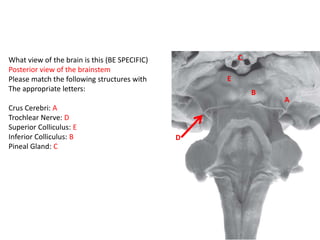

What view of the brain is this (BE SPECIFIC)

Posterior view of the brainstem

Please match the following structures with

The appropriate letters:

Crus Cerebri: A

Trochlear Nerve: D

Superior Colliculus: E

Inferior Colliculus: B

Pineal Gland: C

C

B

E

A

D